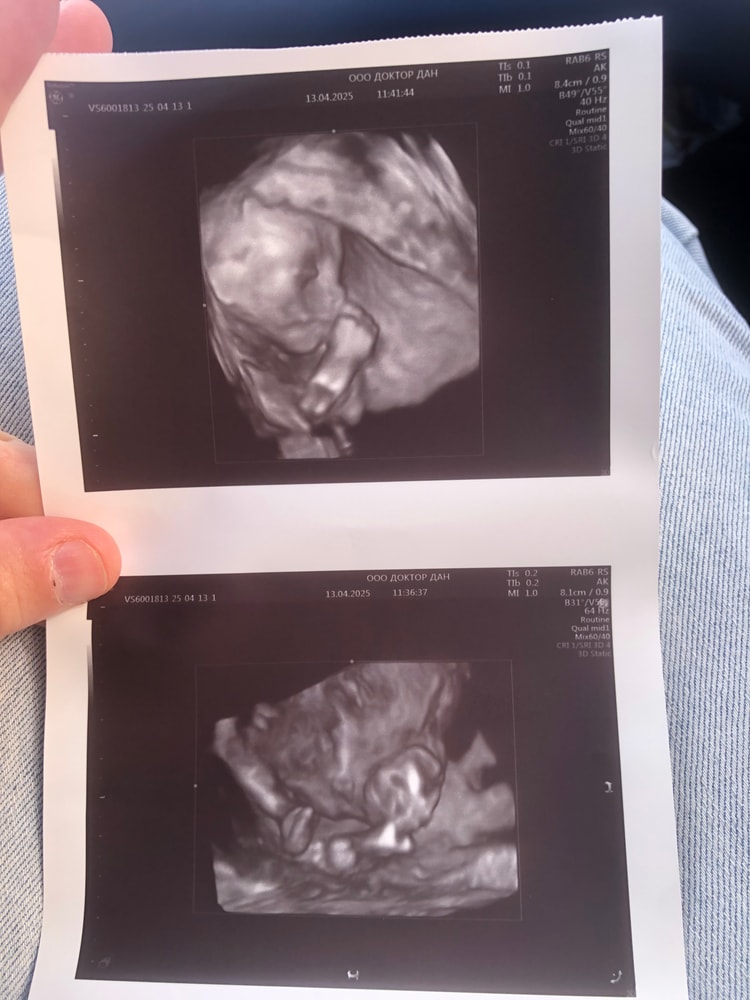

У вас 50/50 мальчик/девочка 🤭 Или вы думаете, что здесь экстрасенсы?! Если уж врач определить не смог. Моя тоже очень долго пряталась, как только врачи (ходила к разным) не пытались подлезть посмотреть. Я думала уже до родов не узнаю.

Мне тоже больше на девочку похоже )

Кажется девчуля 💕а вы кого ждёте если не секрет?

Alania0909, если у вас срок больше 16 недель то там уже должен быть виден писюн если это мальчик🤭🤭🤭а на фото писюна нет поэтому я думаю скорее всего девочка😍в любом случае пусть ваш ребёнок будет здоровым это самое главное❤️А так если точно узнаете напишите пожалуйста кто там ато мне уже реально интересно стало🤭кстати мне тоже в 16 недель предполагали мальчика с первой дочкой🤭во вторую беременность мальчика сразу увидели в 13 недель)а в третью беременность тоже в 12 недель мальчика предположили а по крови девчулька и родилась тоже девчуля)это было в бельгии

По этому снимку не очень понятно. В 2Д снизу лучше смотреть.

Мне кажется это девочка. Уж слишком маленькая мошонка.